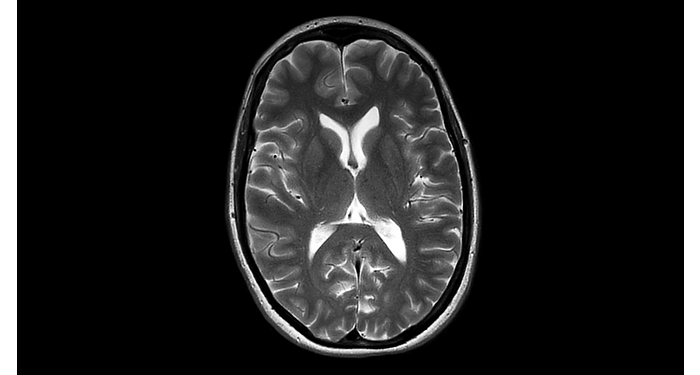

Hospital Eramse, Bélgica

Imágenes de la IRM de campos oscuros de un paciente con VIH con vasculitis cerebral

Las imágenes de campos oscuros ayudaron a sugerir el diagnóstico y elegir el tratamiento.